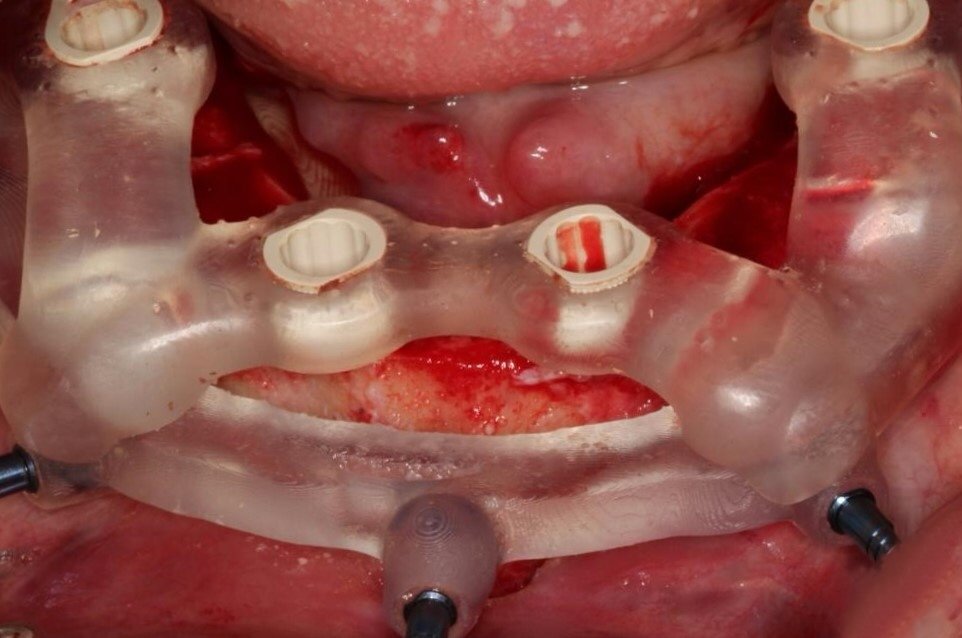

2. "All-on-X" Full-Arch Restoration

For patients who are missing most or all of their teeth in an arch, the All-on-X protocol (often All-on-4 or All-on-6) is a life-changing solution. Instead of one implant per tooth, we strategically place a specific number of implants (the "X") to support a full bridge of teeth.

• How it works: The prosthetic teeth are screwed directly onto the implants.

• Experience: It is non-removable by the patient. It feels the most like natural teeth, offers maximum biting power, and does not cover the roof of the mouth.

Stability: High. It stays in 24/7 and is cleaned just like natural teeth (with specialized flossing tools).